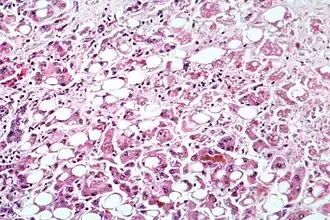

| Doença hepática alcoólica evidente por transformação gordurosa, morte celular e corpos de Mallory | |